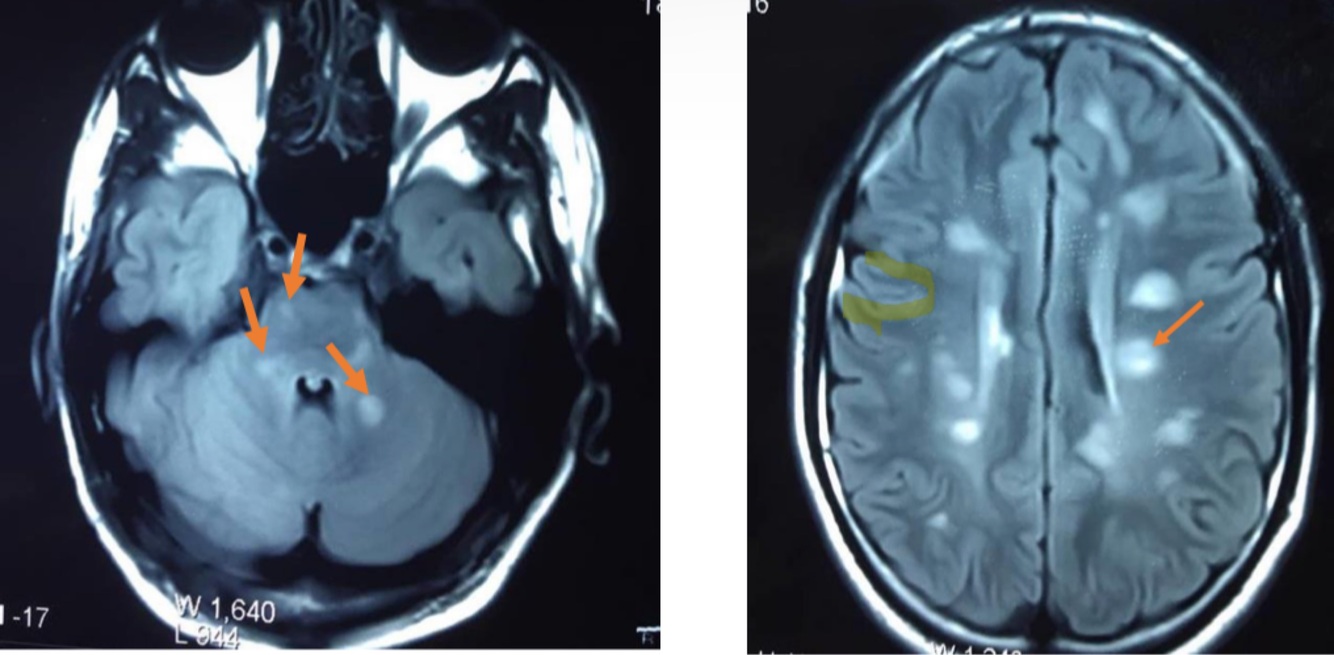

Diagnose

what do you see